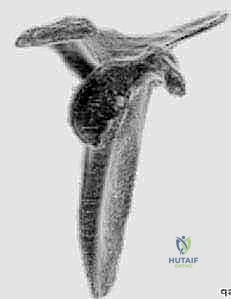

متلازمة "الكمثرى المقلوبة" (Inverted Pear Shape)

في الحالة الطبيعية، يكون الجزء السفلي من التجويف الحقاني أوسع من الجزء العلوي (شكل الكمثرى الطبيعي). ولكن مع تآكل العظم الأمامي السفلي، يفقد التجويف الحقاني عرضه في هذه المنطقة الحرجة. النتيجة هي أن الجزء العلوي يصبح أوسع من الجزء السفلي، مما يخلق شكل "الكمثرى المقلوبة".

الشكل 3 • تقييم دقيق لحجم العظم المفقود من الحافة الأمامية للتجويف الحقاني، وهو المعيار الأساسي لتحديد نوع التدخل الجراحي المطلوب.

الشكل 4 • يوضح كيف أن فقدان العظم يقلل من مساحة التلامس المفصلي، مما يسهل خروج رأس العضد من مساره الطبيعي.